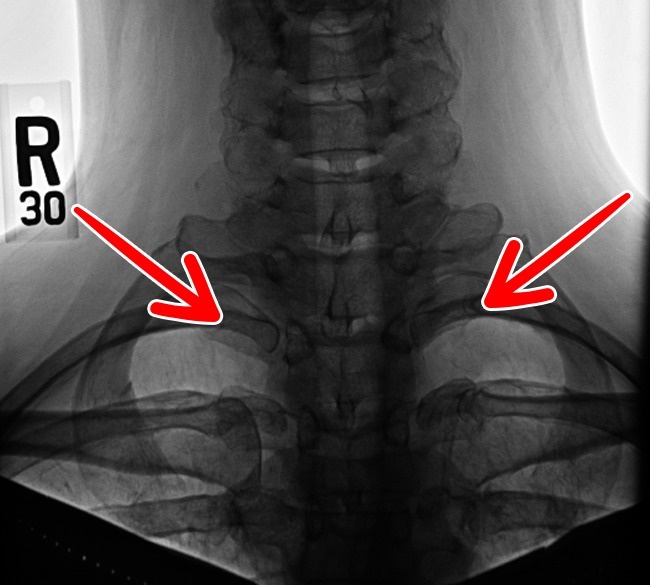

5. צלעות הצוואר